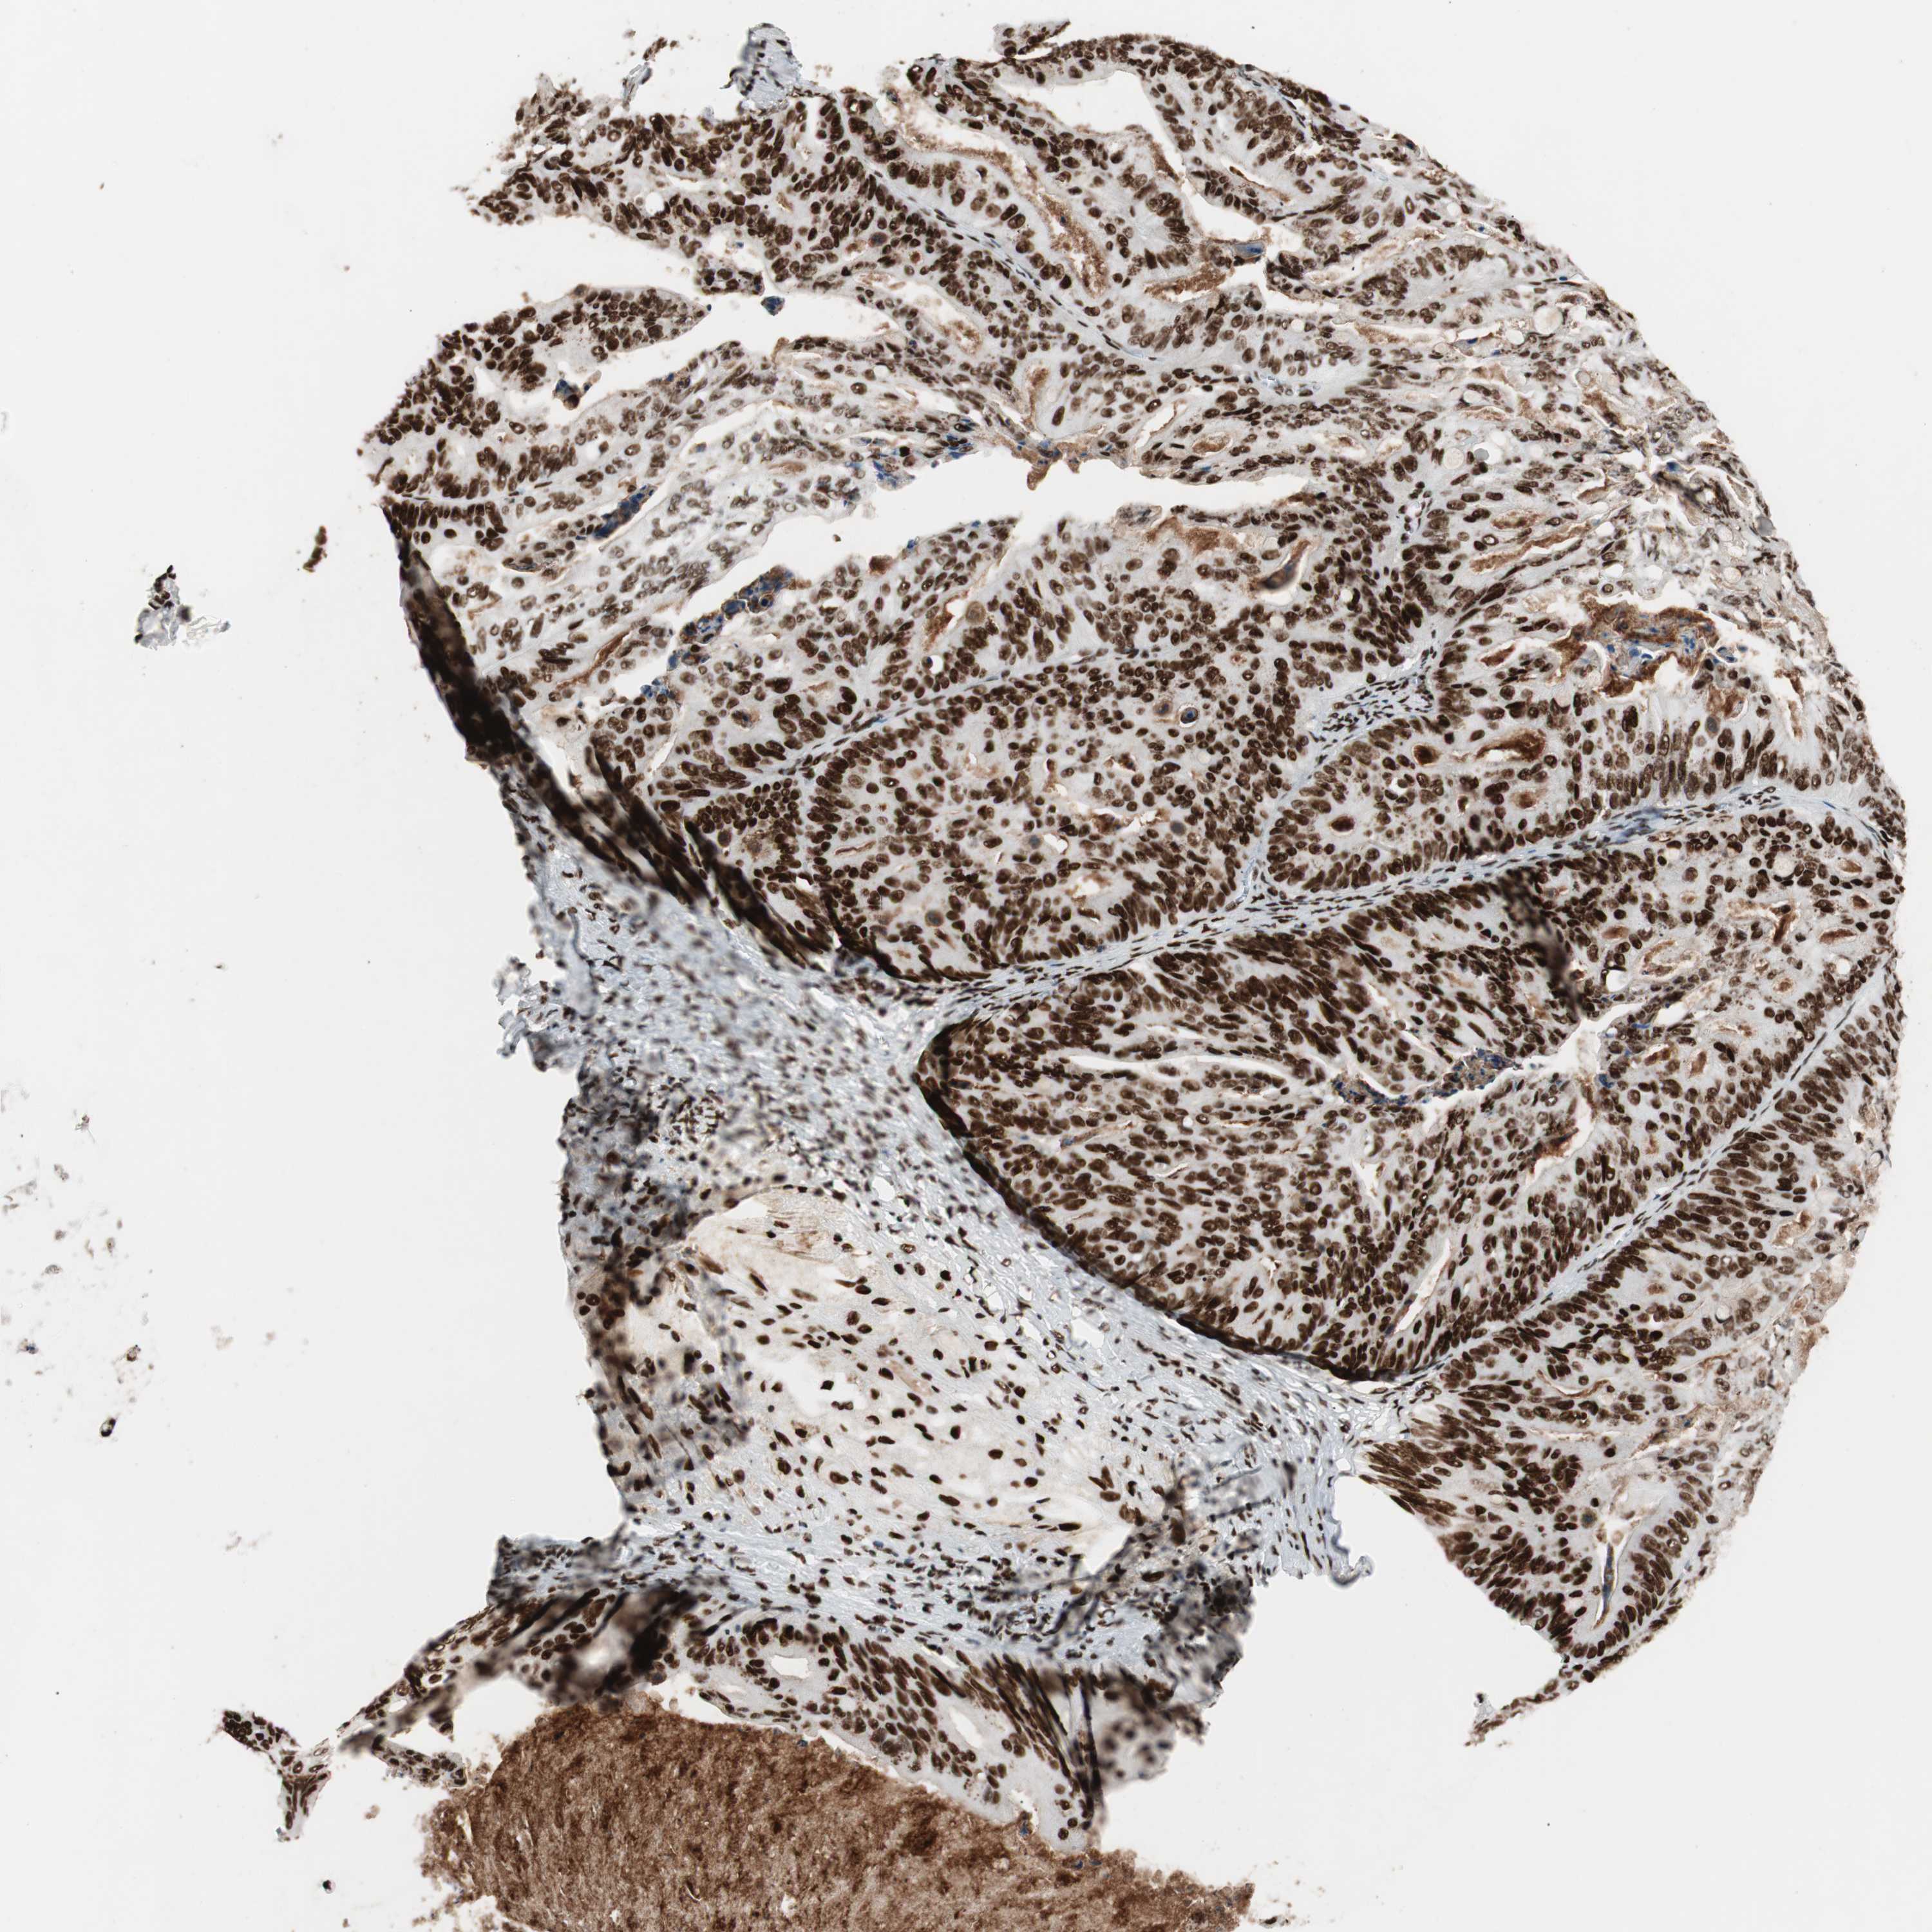

OVARIAN CANCER - Protein expressioni

A mouse-over function shows sample information and annotation data. Click on an image to view it in a full screen mode. Samples can be filtered based on level of antibody staining by selecting one or several of the following categories: high, medium, low and not detected. The assay and annotation is described here.

Note that samples used for immunohistochemistry by the Human Protein Atlas do not correspond to samples in the TCGA dataset.

Antibody stainingi

Antibody staining in the annotated cell types in the current human tissue is reported as not detected, low, medium, or high, based on conventional immunohistochemistry profiling in selected tissues. This score is based on the combination of the staining intensity and fraction of stained cells.

Each image is clickable and will lead to virtual microscopy that enables deeper exploration of all samples and also displays staining intensity scores, fraction scores and subcellular localization as well as patient and tissue information for each sample.

Antibody HPA012510

Antibody CAB008388

Staining

High

Medium

Low

Not detected

Intensity

Strong

Moderate

Weak

Negative

Quantity

>75%

75%-25%

<25%

None

Location

Nuclear

Cytoplasmic/membranous

Cytoplasmic/membranous,nuclear

Cystadenocarcinoma, serous, NOS

Carcinoma, endometroid

Cystadenocarcinoma, mucinous, NOS

Carcinoma, NOS